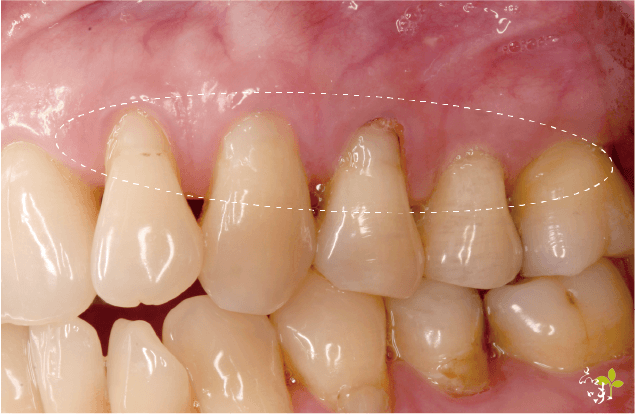

牙齦萎縮的現象

- 某幾顆牙齒齒頸部露出、形成一個 V 字型。

- 假牙邊緣外露,牙冠以下露出來。

- 牙縫有變大的傾向。